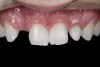

(3.) After resin-based composite bonding of the three incisors.

Figure 3

A 14-year-old patient presented to the office with his mother (Figure 1). His chief complaint involved the large spaces between the teeth created by his missing right maxillary lateral incisor and his small left maxillary lateral incisor. He desired to replace the missing tooth with an implant and create a beautiful smile. Upon examination, he was found to have a class I canine and molar relationship, but because he had a tooth size/arch size discrepancy and space distal to the right central incisor, the remaining incisors had drifted to the right. The left maxillary lateral incisor was peg-shaped and in a cross bite position. Studies have shown a clear association between congenitally missing teeth and reduced tooth size.59-62 Because he was only 14-years-old at the time and could not have implants placed until the cessation of growth (somewhere in the vicinity of 22 years old), he was sent to the orthodontist for alignment of the teeth.16,17 After 2 years of orthodontics, the appliances were removed, and his tooth coloration was improved using carbamide peroxide bleaching (Figure 2). Because some form of provisional needed to be placed until he was finished growing, a double-wing metal resin-bonded bridge was chosen. As discussed earlier, this is the ideal transitional prosthesis for patients that have congenitally missing maxillary lateral incisors. The benefits of this type of prosthesis include its ability to be removed and rebonded during the surgical phase of treatment and its ability to retain the roots in their proper position after orthodontic treatment.16 The final plan for the patient was to increase the width of the central and the maxillary left lateral incisor, utilizing porcelain laminate veneers to achieve the appropriate width/length ratio of 80%. A wax-up was created to idealize tooth size, a putty matrix was made from the wax-up to facilitate bonding of the incisors, and a non-precious, double-wing metal resin-bonded bridge was fabricated for lateral incisor replacement. Once the teeth were bonded to ideal size, the “Maryland Bridge” was fabricated from a polyvinyl arch impression with the newly bonded teeth (Figure 3). The metal frame was cast from a non-precious alloy to allow for fabrication of a very thin frame and to create a better surface for bonding. After sandblasting the internal aspect of the frame with CoJet™ silica (3M ESPE), accomplishing salinization, and executing cementation with a dual-cure resin cement, a fairly good adhesion to the frame was anticipated.29 The enamel surface was etched with phosphoric acid for 30 seconds, the primer (Single Bond Plus, 3M ESPE) was applied to both the internal surface of the sandblasted framework and the etched enamel, and the bridge was cemented with RelyX™ ARC (3M Espe) dual-cured resin cement (Figure 4 and Figure 5).